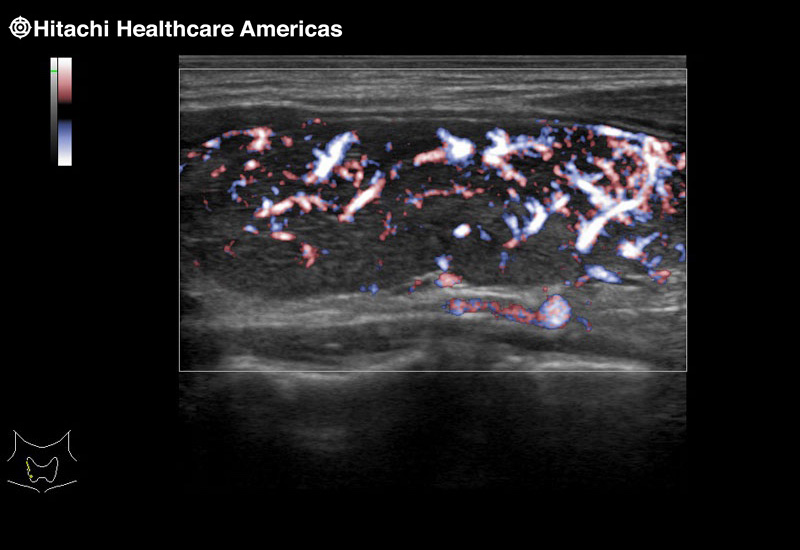

Superior guidance for all applications

Fujifilm Healthcare Americas is committed to designing tools that help surgeons navigate inside the human body and provide the necessary information to immediately make critical surgical decisions.

Fujifilm Healthcare's dedication to Surgeons provides outstanding ultrasound technology, professional support and the specialized tools necessary to best perform comprehensive real-time ultrasound imaging in Breast Surgery, General Surgery, Laparoscopic Surgery, Neurosurgery, Robotic Surgery and Surgical Oncology.